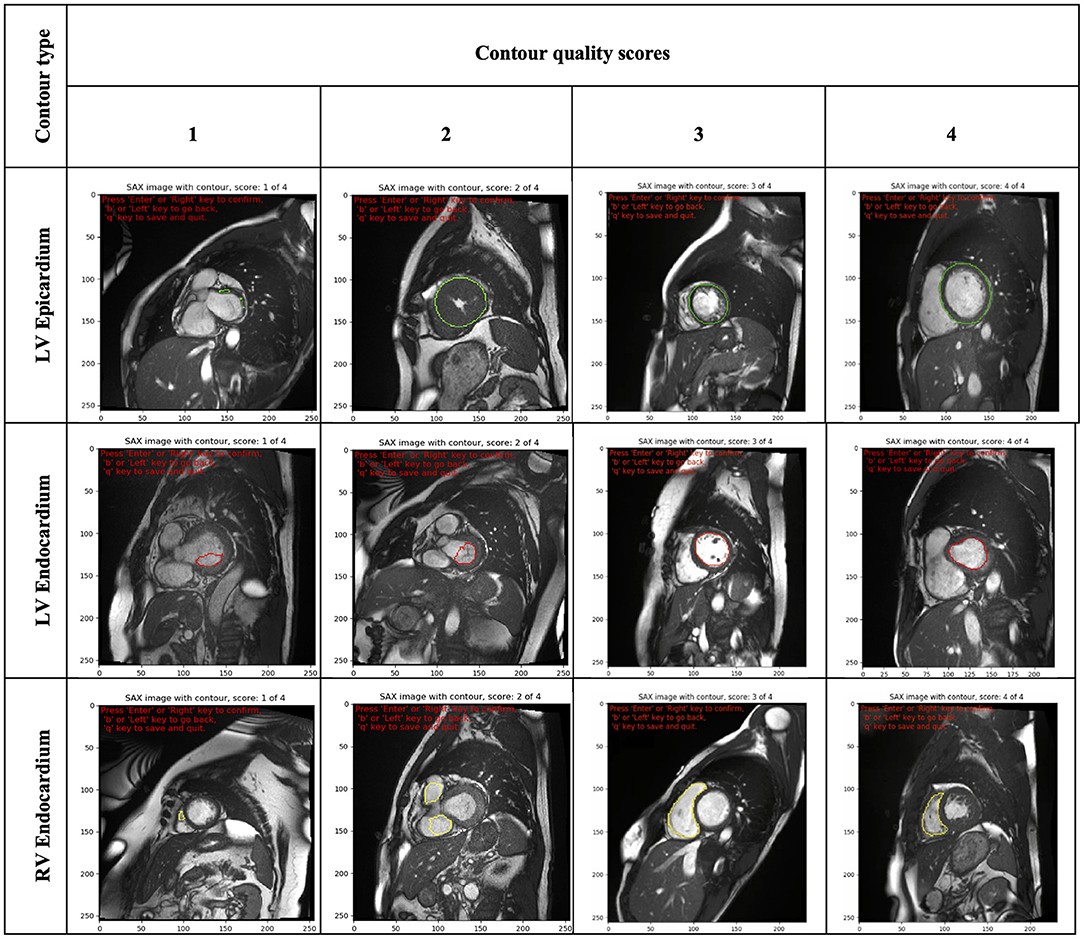

The scoring rubric included scores ranging from one to four. A score of one was assigned to significantly inaccurate segmentation and thus considered clinically unacceptable. A score of two was given to bad quality contours, which required significant manual changes to make them clinically acceptable. A score of three was assigned to fair or clinically acceptable contours with minor or negligible inaccuracies in the segmentation considered not clinically relevant. Finally, a score of four was assigned to contours considered of good quality with no changes needed.

Furthermore, as images were presented independent of spatiotemporal context, contour quality assessment was mainly based on how well the area of the delineated structure was approximated. Consequently, small contours and small deviations were rarely assigned a quality score of ≤2, as that was considered not clinically relevant. Special attention was given to the RV endocardial contour, especially at SAX basal slices, for which two separate regions may be contoured. In such cases, a score of three was given if the two disjoint contours sufficiently encompassed the underlying anatomy; otherwise, they were scored as two or one. An illustration of some contours to which raters assigned different quality scores is shown in Figure 2.

Figure 2. Illustration of some contours (LV epicardial, LV endocardial and RV endocardial) showing the range of quality scores (from 1 to 4). LV, left ventricle; RV, right ventricle.